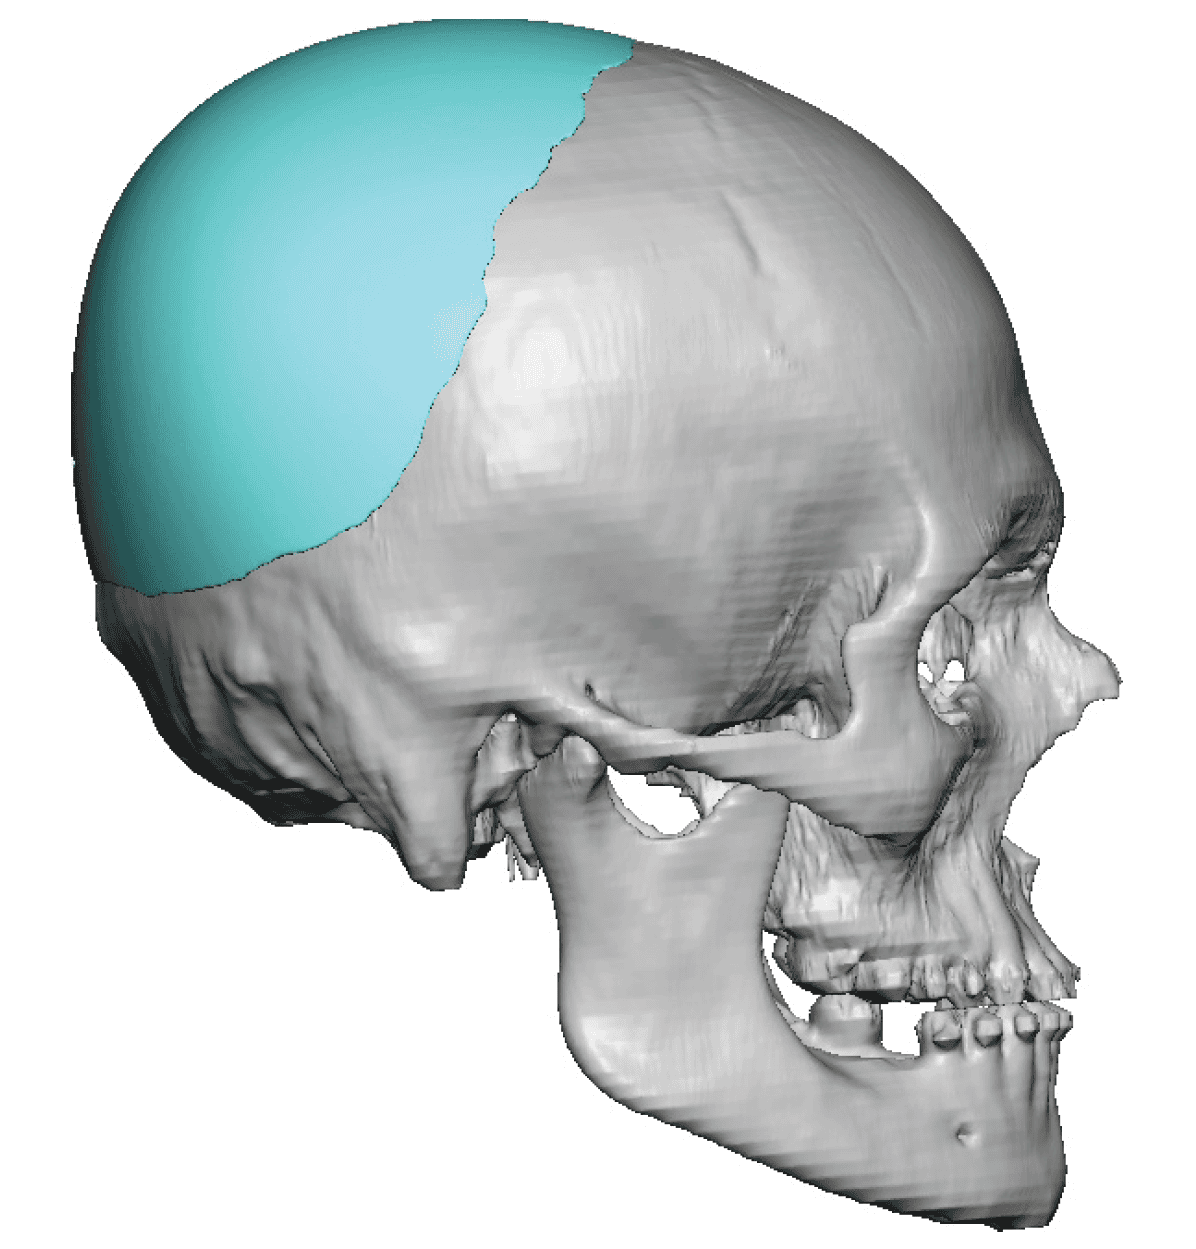

Patient 49

Desire for further skull augmentation after a primary skull implant.

Five years after an initial custom skull implant placement a new custom skull implant that increased the volume by 35% was placed.

Desire for further skull augmentation after a primary skull implant.

Five years after an initial custom skull implant placement a new custom skull implant that increased the volume by 35% was placed.